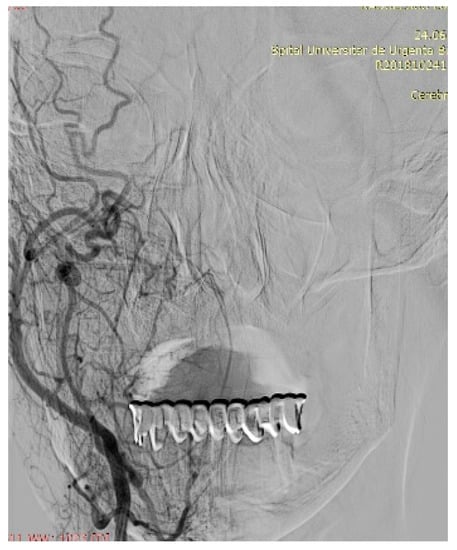

4. Imagery in Extracranial FNSs

7. Therapeutic Strategies in the Management of FNS Extracranial Segment